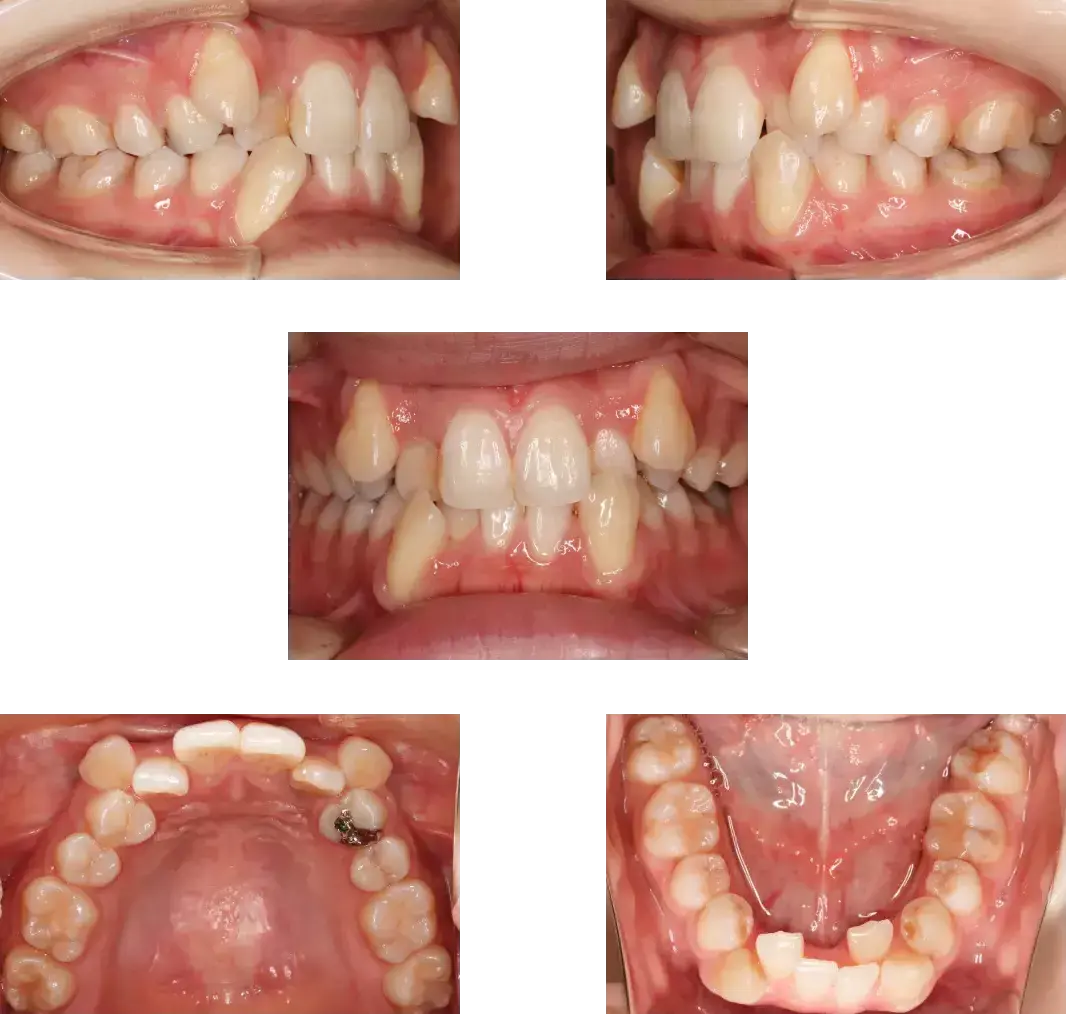

[症例:7] 小児矯正症例

[症例:8] 小児矯正症例

主訴 | 前歯が1本内側に生えている。 |

診断名 | 幅径の不一致、前歯部分反対咬合症例 |

治療内容 | 取り外し式の装置で上顎骨の幅径拡大を行い、前歯の被蓋改善を行った。 |

年齢 | 8歳 |

装置 | 関口先生方式前歯プッシュプレートとシュワルツの拡大装置ミックスの設計 |

抜歯部位 | なし |

動的治療期間 | 24か月 |

治療費(施術料) | 385,000円 |

リスク・副作用 | 被蓋改善時の前歯歯根吸収、痛み、術後の変化 |

主訴 | 上の2番目の前歯が内側に生えてきた |

診断名 | 叢生症例、永久歯萌出スペース不足 |

治療内容 | 取り外し式の装置で上顎骨の拡大を行い、その後前歯をアクティブプッシュ。 |

装置 | シュワルツの拡大装置、上顎2×4装置 |

動的治療期間 | 26か月 |

治療費(施術料) | 500,000円 (RIVAGE式 子どもinclusive) |

リスク・副作用 | 痛み、軽度の歯根吸収、術後の変化 |